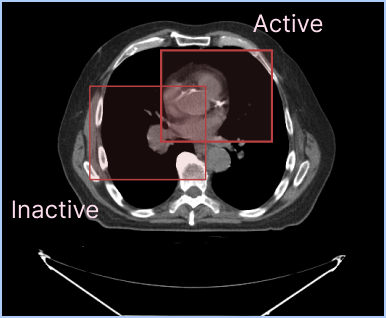

As you see in the picture above, you can display two different labelmaps at the same time. Default configuration for active segmentation representation is to have a higher outline width value than the inactive segmentation representation in order to make the active segmentation representation more visible.